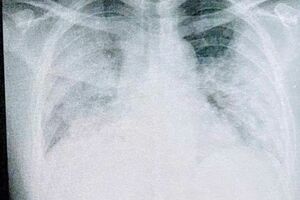

瀬川達也さん(仮名・37歳)はこの夏、コロナに感染し、医師に「死ぬかもしれない」と宣告を受けた。基礎疾患もなく、大きな病気をしたこともない男性だ。至って元気だったが、コロナ感染後に重症化。入院前には血中酸素飽和度が「72%」という極めて危険な数値にもかかわらず、苦しさの自覚症状がない「ハッピー・ハイポキシア」の状態に陥った。さらに三度の入院に至るまでの経緯を、日にちを追って詳しく聞いた。